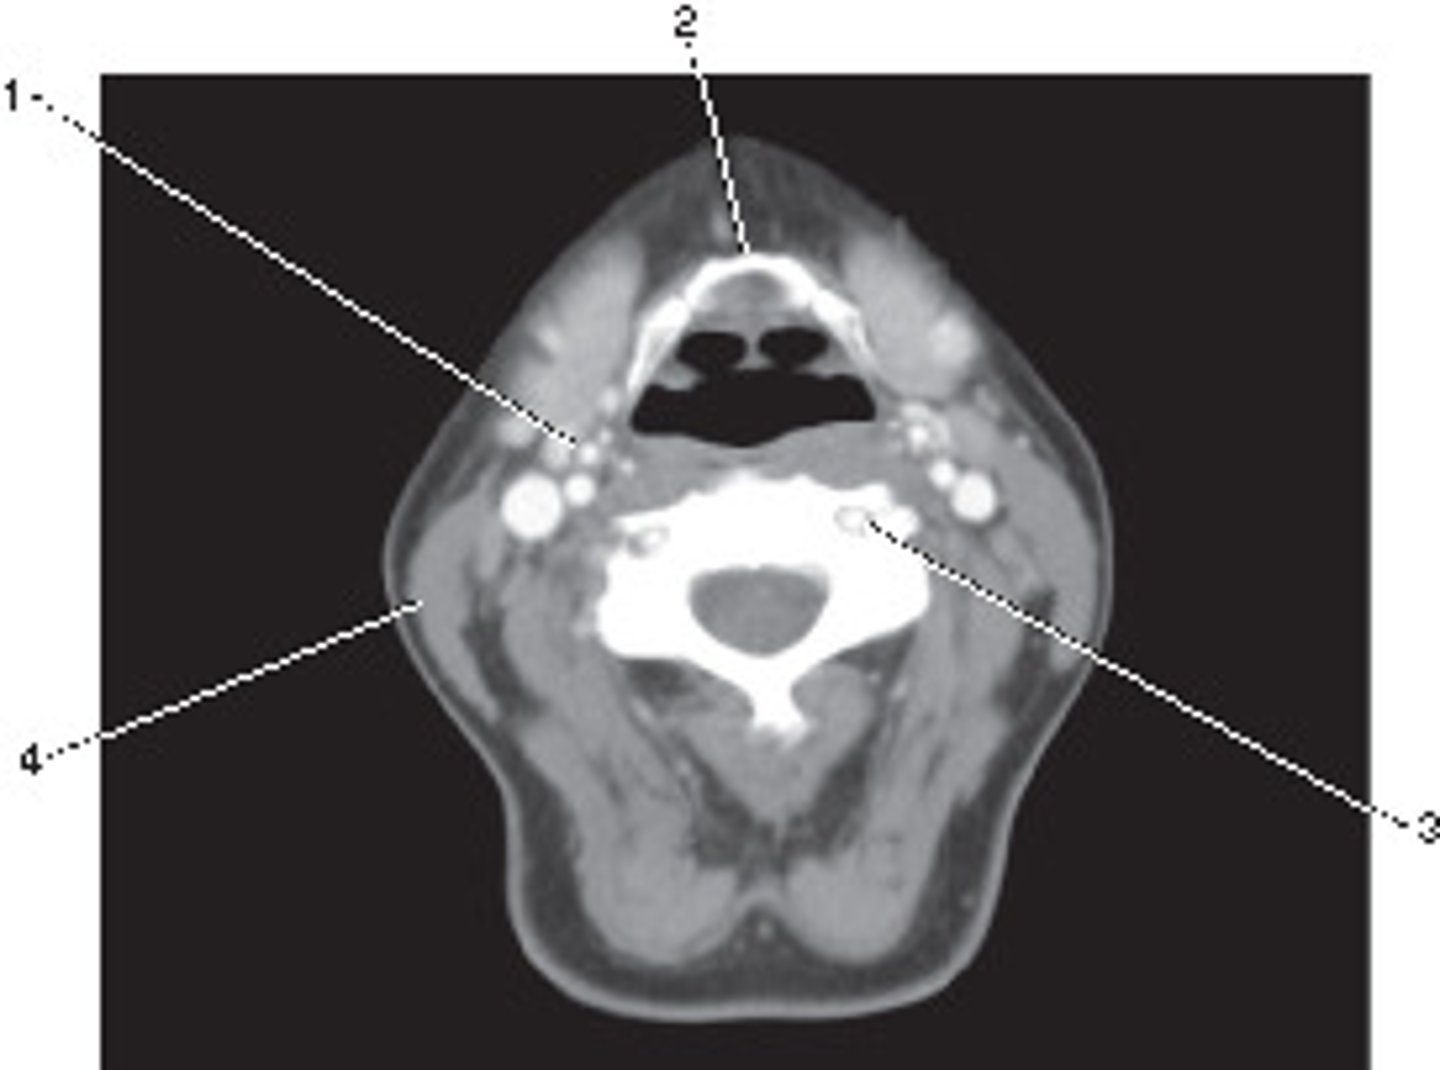

Number 2 corresponds to which of the following?

<p>Number 2 corresponds to which of the following?</p>

Number 4 corresponds to which of the following?

<p>Number 4 corresponds to which of the following?</p>

Common Carotid Artery

Number 5 corresponds to which of the following?

<p>Number 5 corresponds to which of the following?</p>

Retromandibular Vein

Number 3 corresponds to which of the following?

<p>Number 3 corresponds to which of the following?</p>